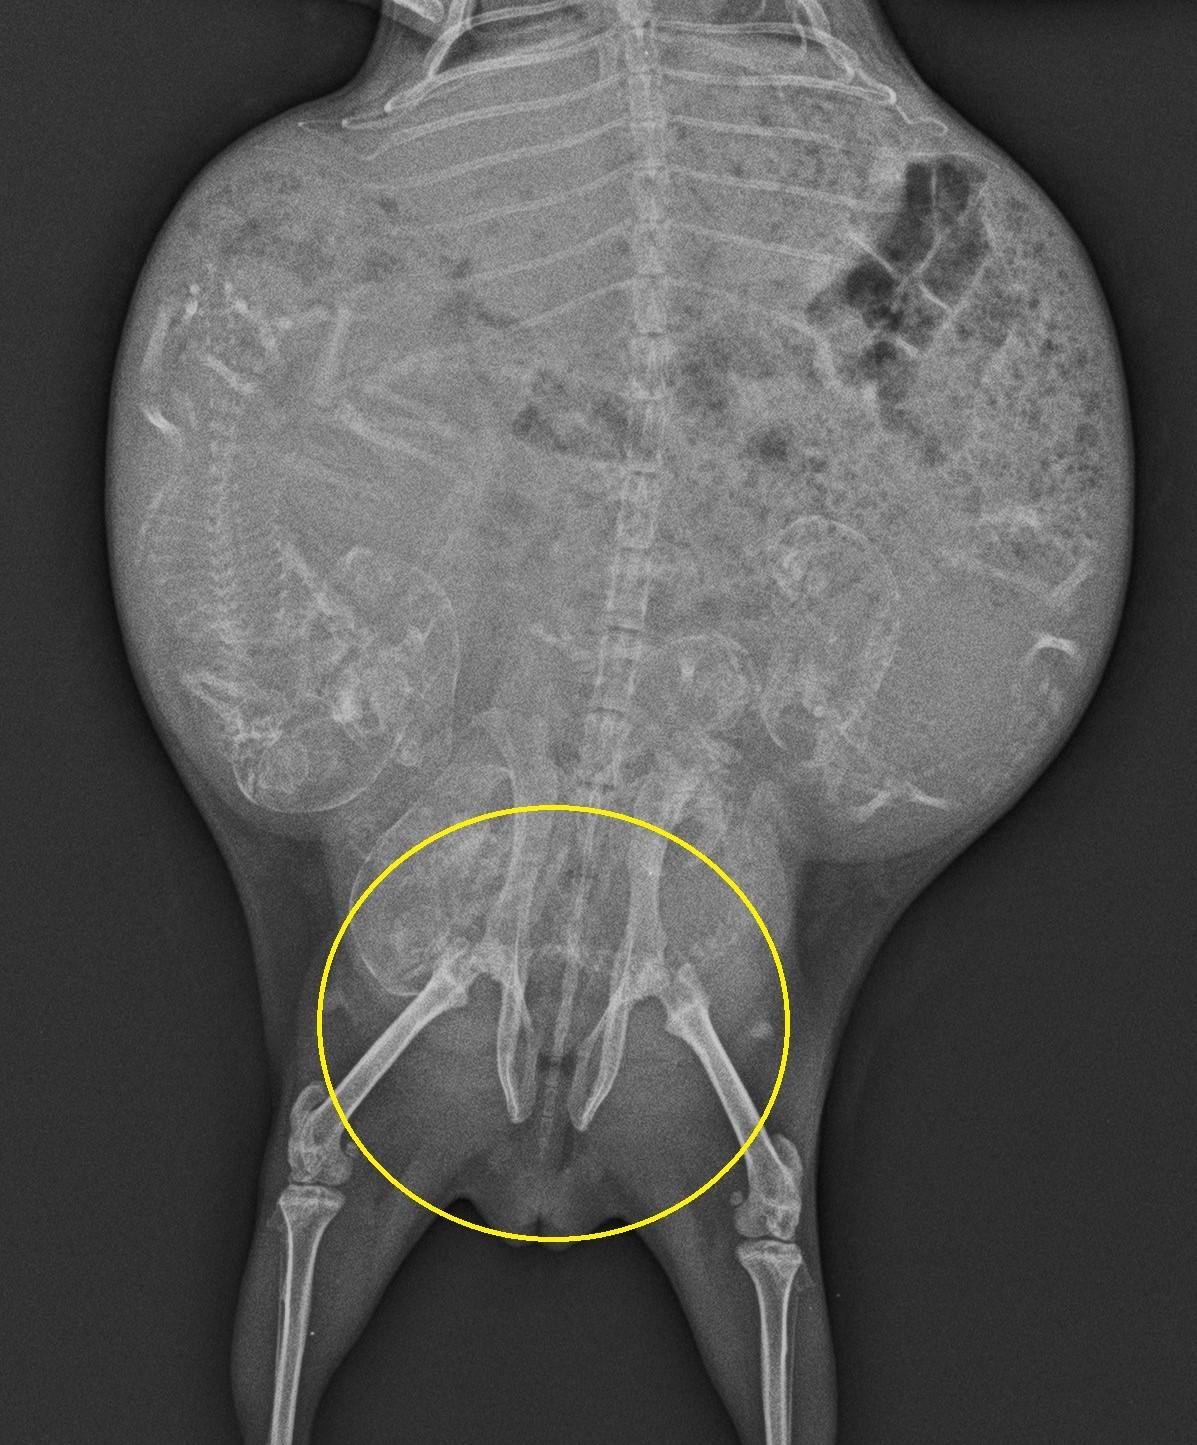

レントゲンでは、骨盤の恥骨結合が1.5㎝以上開き、出産が近いことがわかります。モルモットの成書によると、恥骨結合が1.5㎝まで開くと48時間以内に出産すると言われています。

ちなみに、これはまだ恥骨結合が開いていないレントゲン写真です。

比べるとわかりやすいですよね。